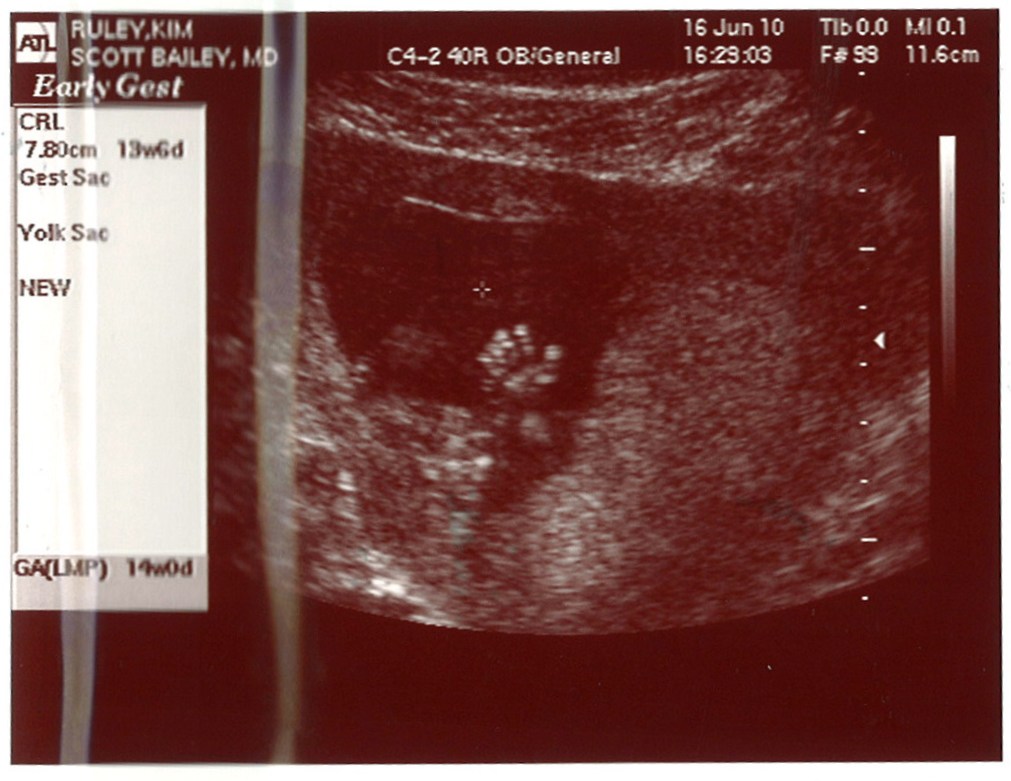

>> Sunday, June 20, 2010

Wednesday we went for an ultrasound and saw a very active baby. The baby was kicking and hands were moving. I'm going to post a pic. We could see the lips, nose, eyes and in one picture a very clear right hand. We're so happy all is going so well!